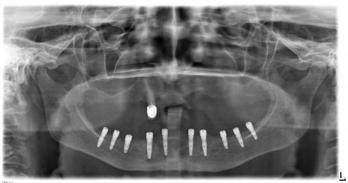

Установка 10

имплантантов на

беззубую челюсть с

помощью компьютерной

программы